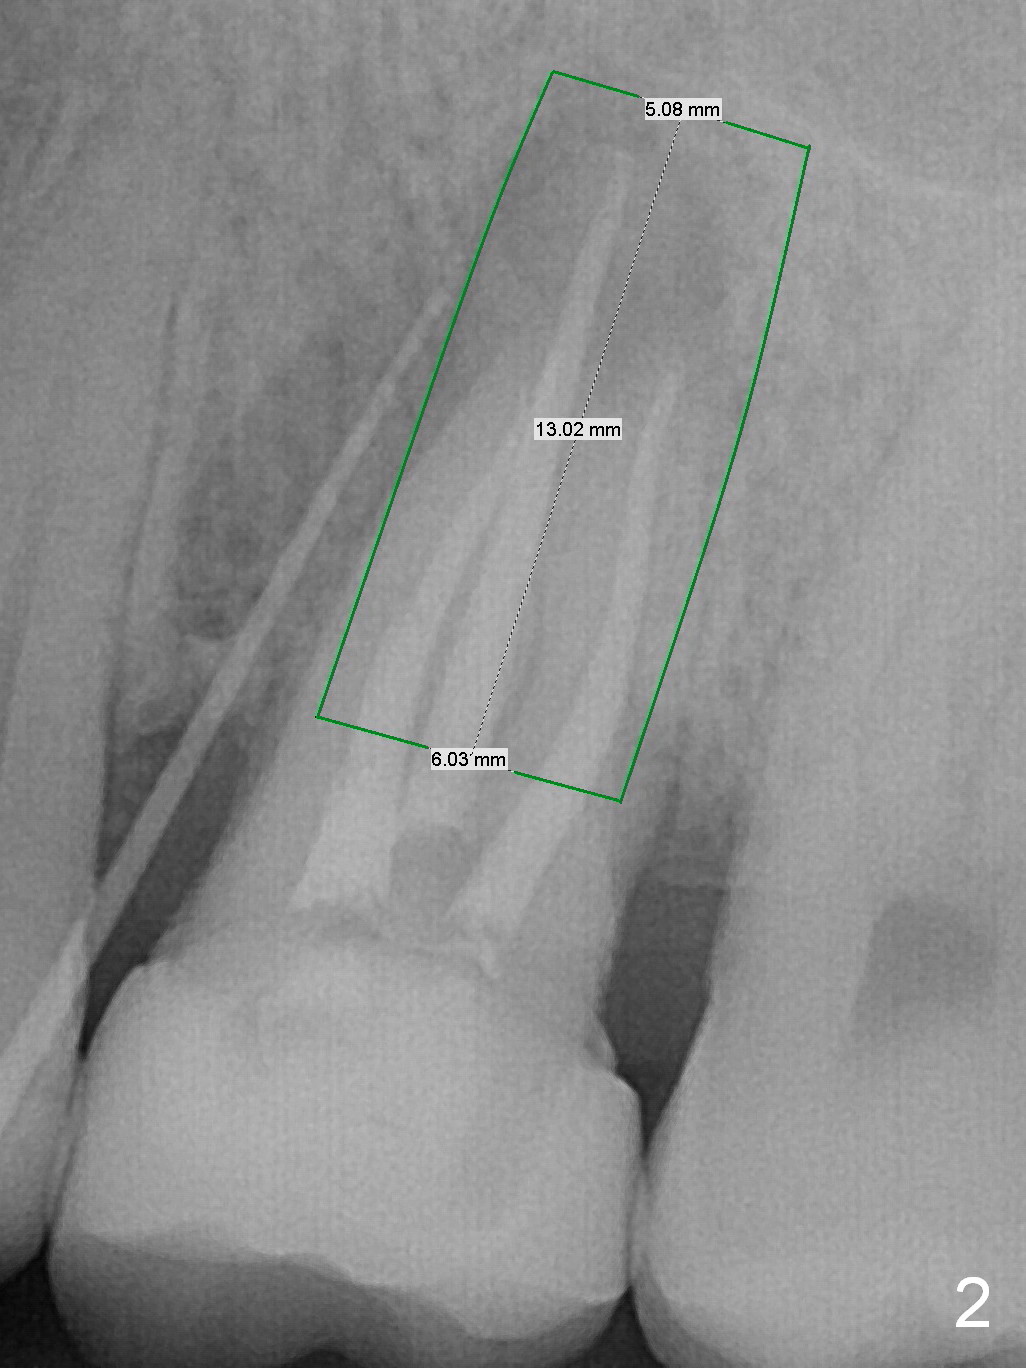

A 34-year-old man has persistent large periradicular radiolucency (Fig.1) after root canal therapy with a fistula (Fig.2). It appears that immediately after extraction (no Antibiotic) a long implant (15 or 16 mm, green outline) should be placed to bypass the bony defect with 2-point fixation (septum and sinus floor; Fig.3 (CBCT sagittal section), 4 (coronal section) red line). A shorter implant, which is placed at the septum (4-5 mm tall), is not expected to be stable. The diameter of the implant is to be determined after sequential osteotomy. The minimal will be 4 mm (Fig.5 axial section) as long as the implant or osteotomy does not perforate the palatal (P) or buccal (B) socket substantially. The bone density at the septum and the sinus floor is 1100 and 200-400 units, respectively. Drills and osteotomes (Tatum or Magic Expanders) will be used for osteotomy in these 2 segments, respectively.